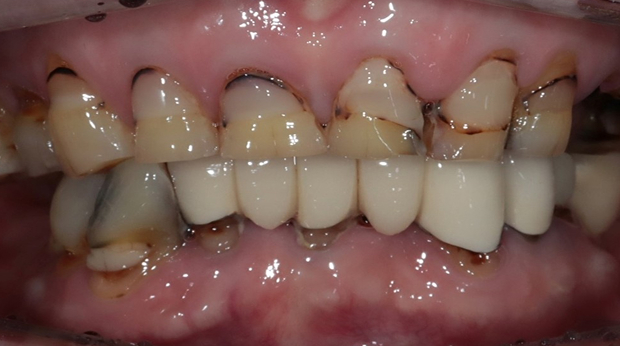

라미네이트